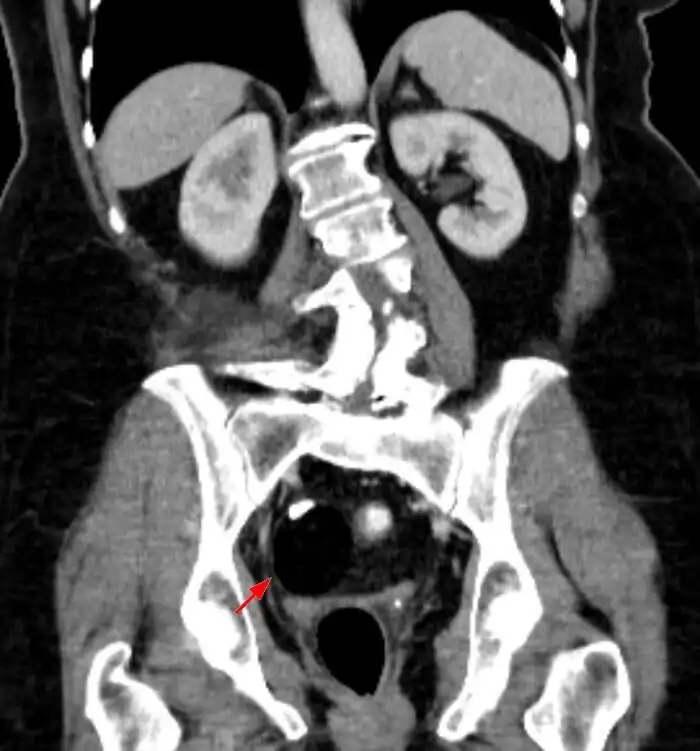

15. «Бывают опухоли с волосами, зубами и даже глазами. Они называются тератомы».